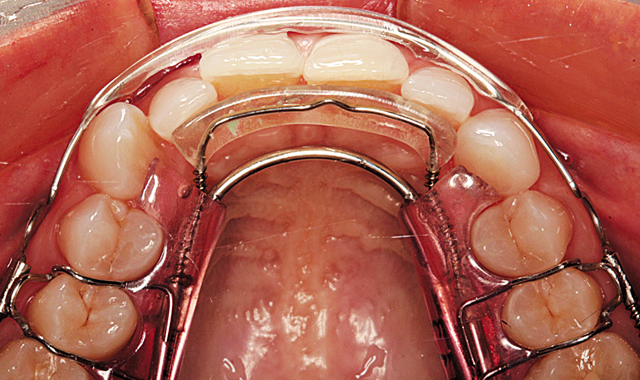

Figure 6 shows the aligners in place from the retracted facial view. The maxillary aligner at placement is shown from the incisal view in Figure 7. In Figure 8, the mandibular aligner is shown in place also from the incisal view.

Fig. 7